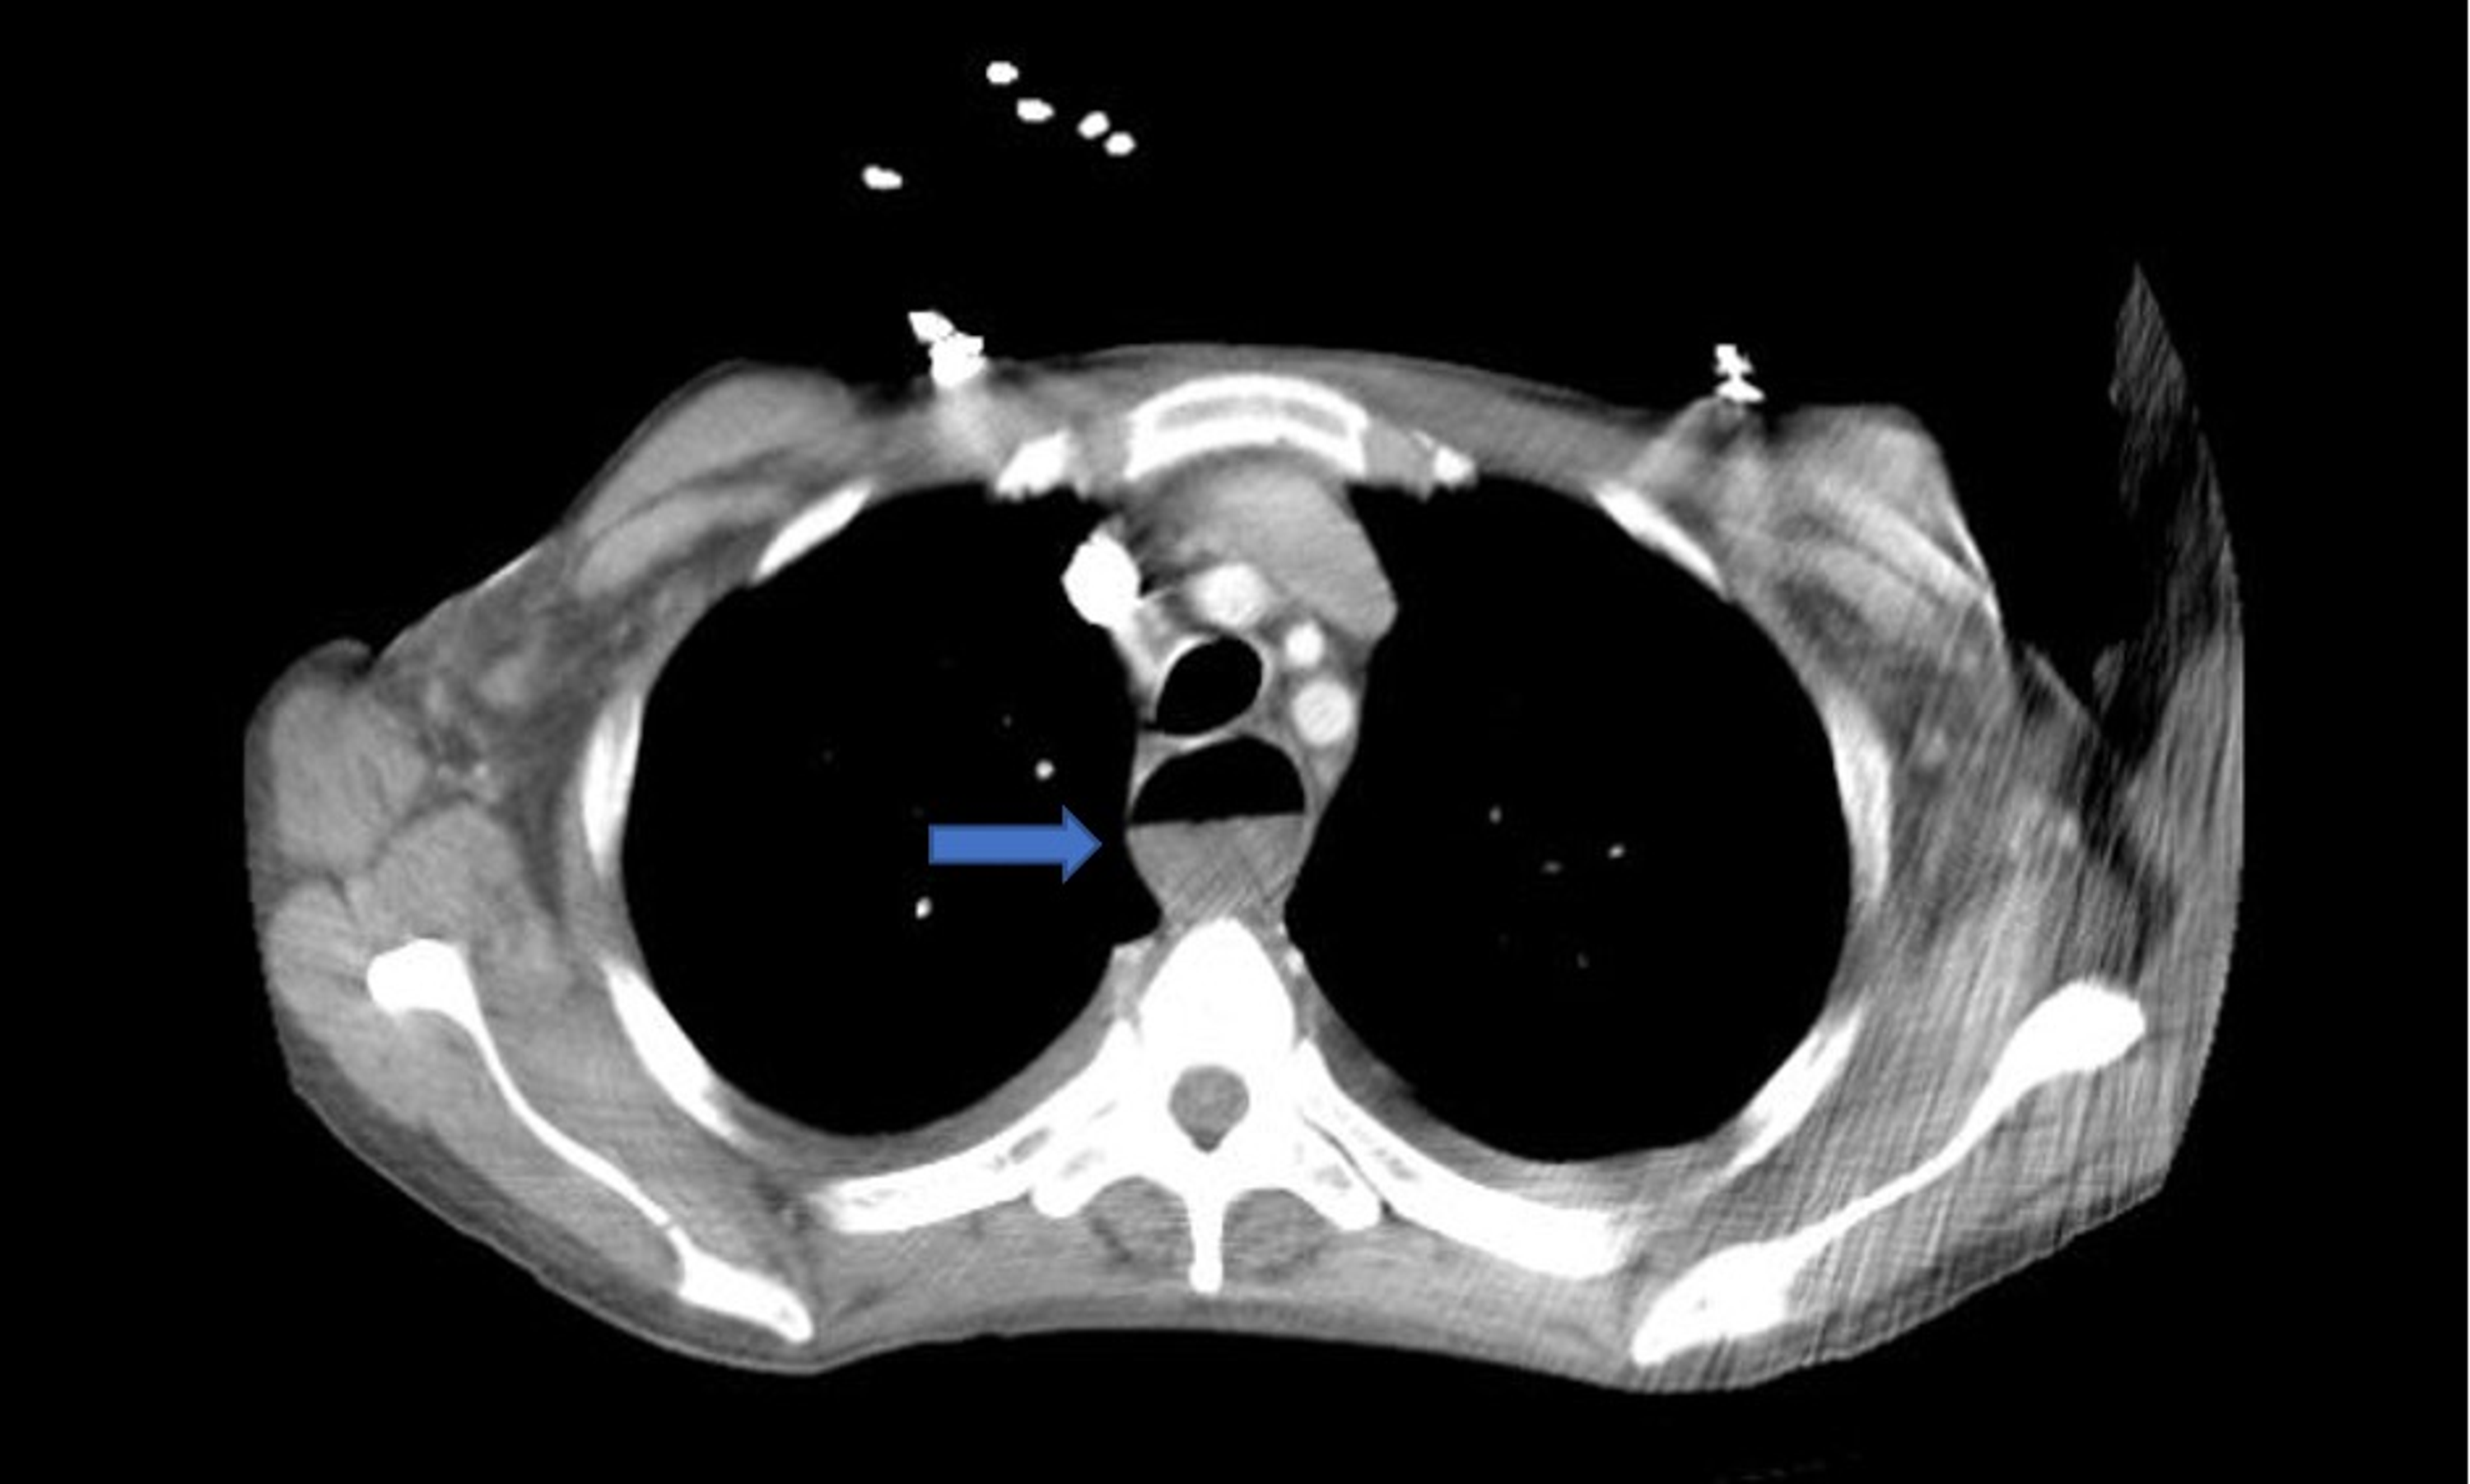

Distal Thoracic Esophagus Air Distended Esophagus The presence of increased esophageal air or distention of the esophagus on a ct scan of the chest may be associated with. A patulous esophagus is a condition characterized by the abnormal widening or opening of the esophagus. It can cause various symptoms. Aerophagia involves swallowing too much air — so much air that you experience symptoms like bloating, gas. Air Distended Esophagus.